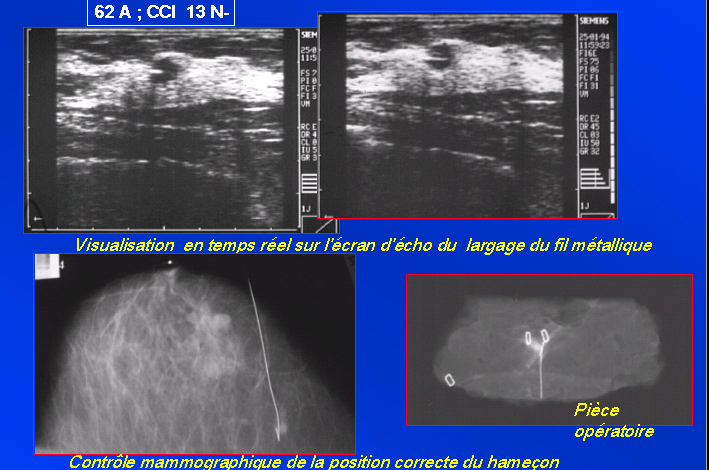

Repérage pré-opératoire

à l’hameçon sous échographie.Harpon dans son aiguille

guide. Abord indirect. Retrait délicat de l’aiguille en laissant

en place le fil harpon. Arrimage du harpon à la peau selon les auteurs.

Radiographies de contrôle face et profil. Compresse stérile pour

pansement.